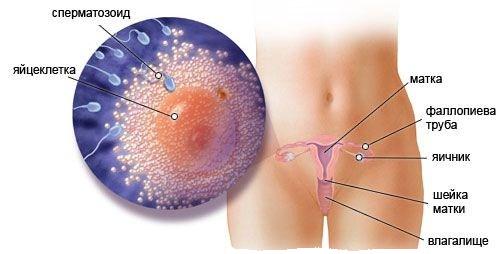

Якщо розглядати це питання з наукової точки зору, то фолікула в цей час продовжує свій розвиток в яєчнику, таким чином виділяється жіночий гормон - естроген. Це є причиною збільшеного статевого потягу на другому тижні. При повному дозріванні фолікул в діаметрі досягає двох сантиметрів. Усередині фолікула збільшується кількість рідини, через це він лопає і недозріла гамета виходить назовні.

Саме в цей проміжок часу, поки яйцеклітина діюча, її можливо запліднити, в такому випадку настає вагітність.